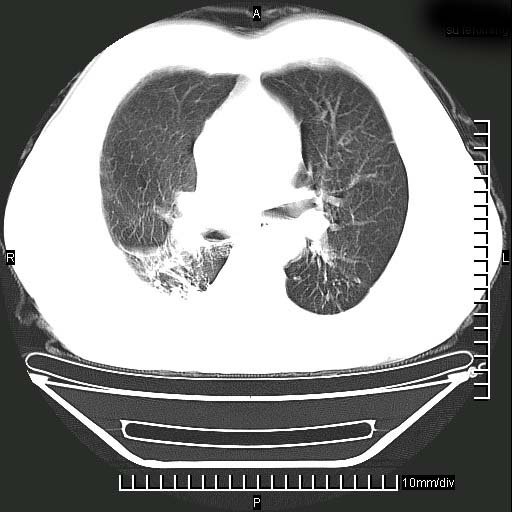

标题: CT24043:胸部增强:男性,60岁

既往肺结核,近10几天,咳嗽,咳痰,右侧胸痛,疼痛较明显,右上肺斑块考虑结核灶胸膜粘连,增强,可惜动脉期没有定好,未见强化,可延迟4分后又见较明显强化,中心见低密度影,如果说结核是边缘强化,可这个灶强化的面积挺大的,让人很挠头。

动脉期